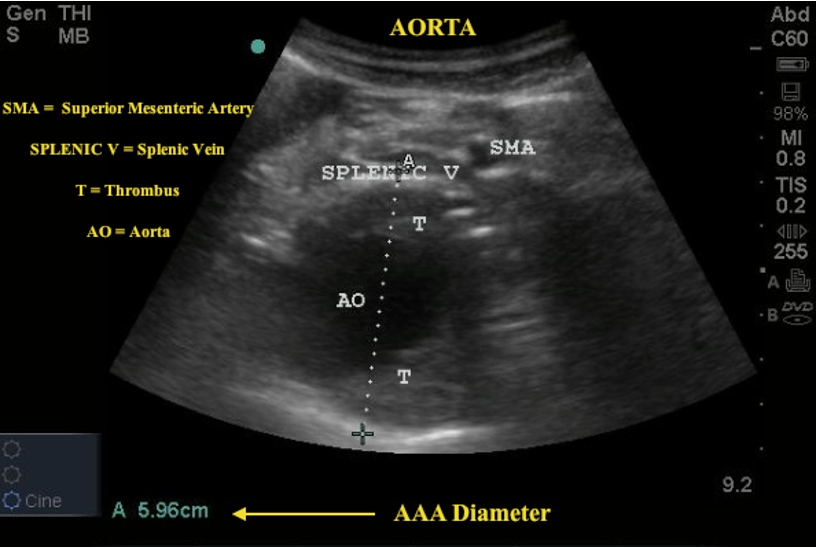

What does this ultrasound refer to

aortic aneurysm